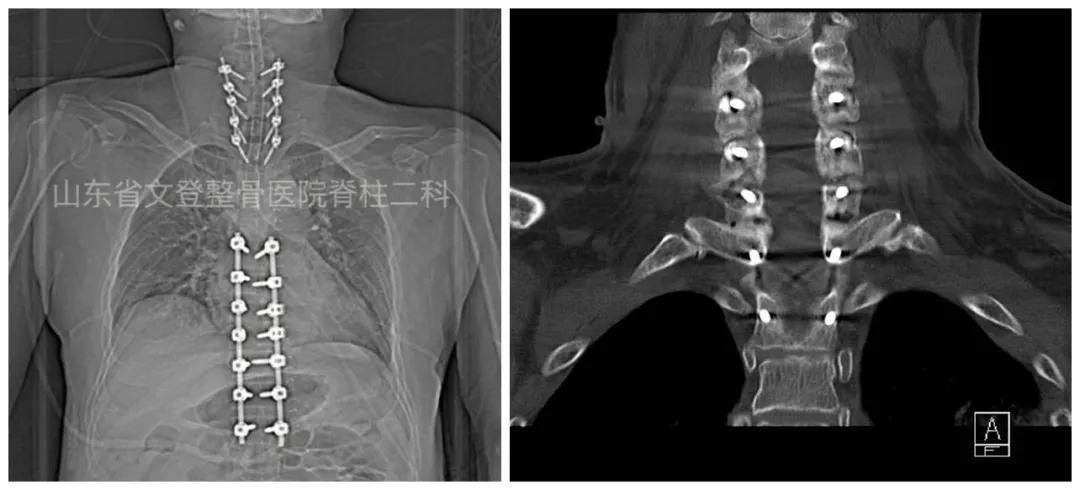

术后CT冠状位

术前颈椎CT 术后颈椎CT解剖复位

术后C5-C7 椎弓根钉